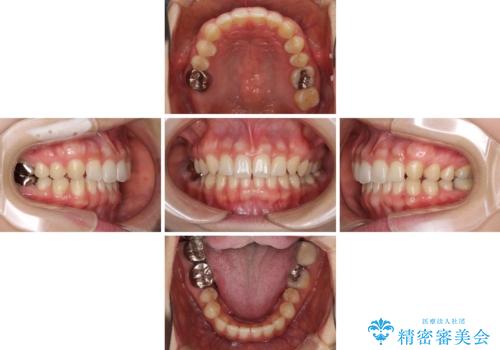

- 前歯の隙間と奥歯の目立つ銀歯を気にして来院された患者様です。

インビザラインにより下顎前歯の隙間を閉じるとともに、奥歯の咬み合わせを改善させることとしました。

矯正治療後には、銀歯のクラウンをセラミッククラウンへ替える補綴治療を行うこととしました。